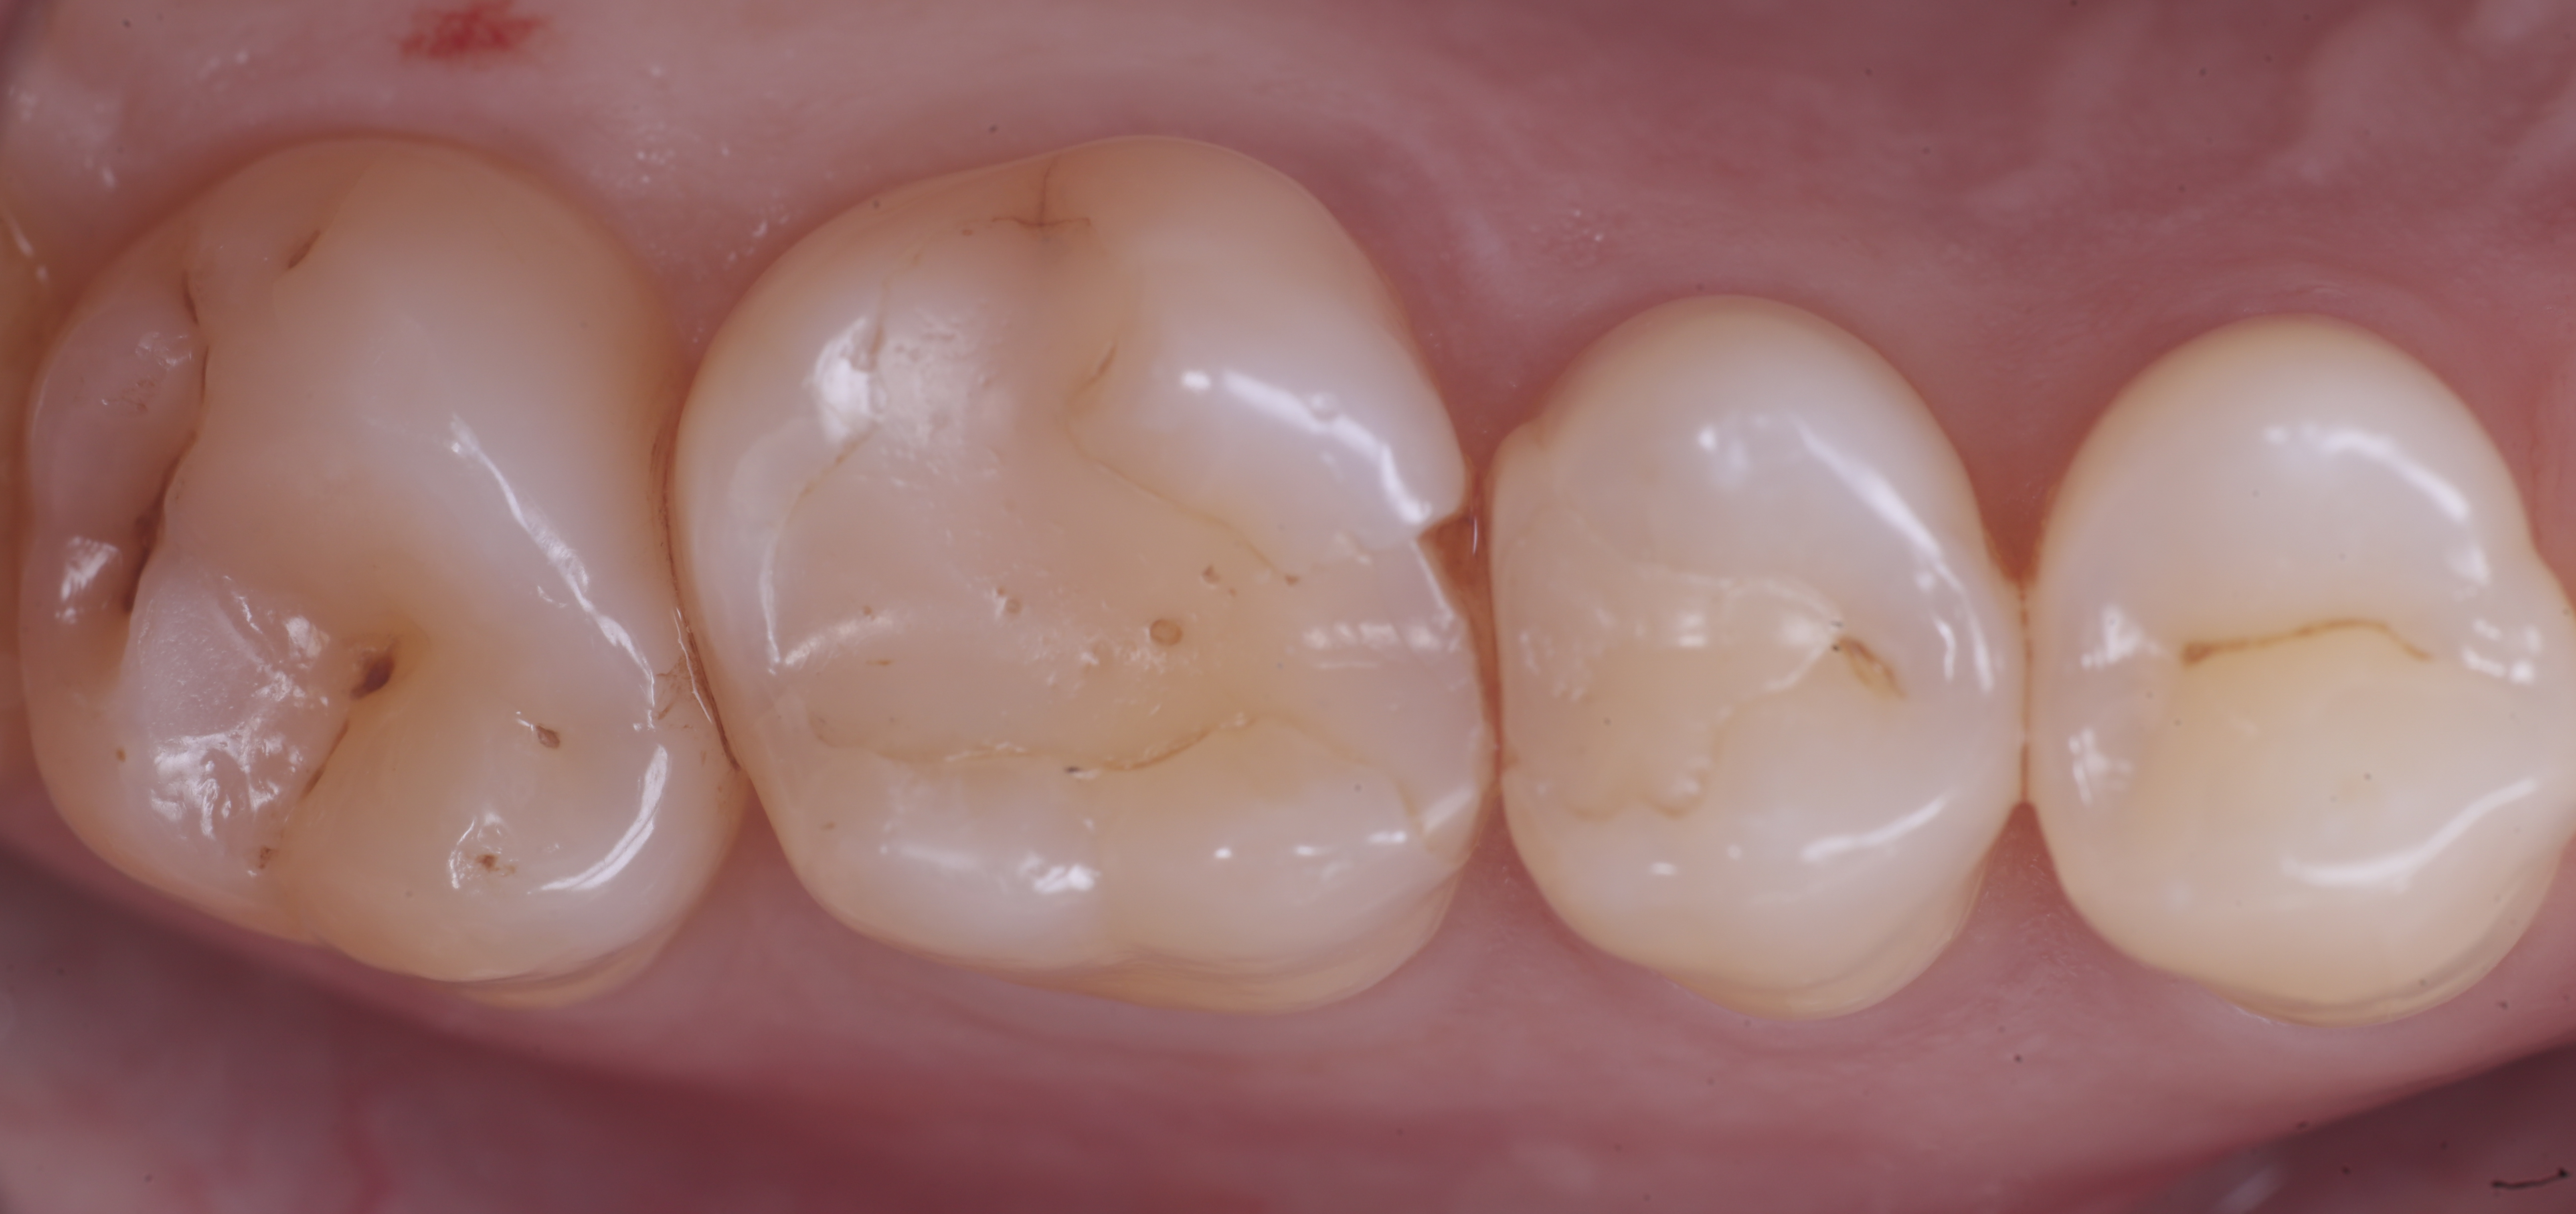

foto 11 Restauri ultimati sotto controllo occlusale